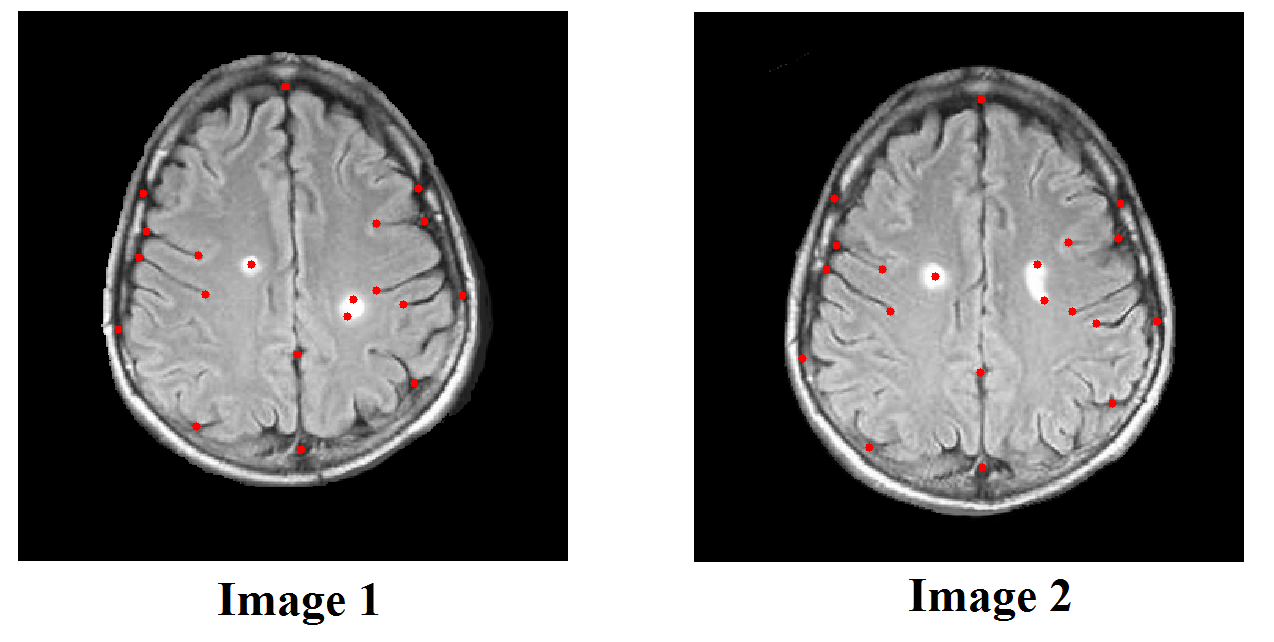

Example 8

We also test the hybrid registration algorithm to register two brain MRIs. Figure 14 shows two human brain images. Corresponding landmark features are labeled on each images. In Figure 15, we show the registration results using different approaches. Figure 15(B) shows the deformed image from Image 1 using the landmark based registration model. If we only use landmarks as constraints to guide the registration, the deformed image is different (see regions in the red boxes) from the target image (as shown in (A)). (C) shows the deformed image from Image 1 using the intensity based registration model. Similarly, the deformed image is very different (see regions in the red boxes) from the target image if only intensity information is used. Notice that the tumor in the red box does not move using intensity based registration. (D) shows the deformed image from Image 1 using the proposed hybrid registration model. The deformed image closely resembles to the target image. The intensity mismatching error is less than 1%, meaning that the registration is very accurate.

Refer to caption

Fig. 14: Two human brain images to be registered. Corresponding landmark features are labeled on each images.

Fig. 15: Registration results of the human brain images using different approaches. (A) shows the target image (Image 2 as in Figure 14). (B) shows the deformed image from Image 1 using the landmark based registration model. (C) shows the deformed image from Image 1 using the intensity based registration model. (D) shows the deformed image from Image 1 using the proposed hybrid registration model.